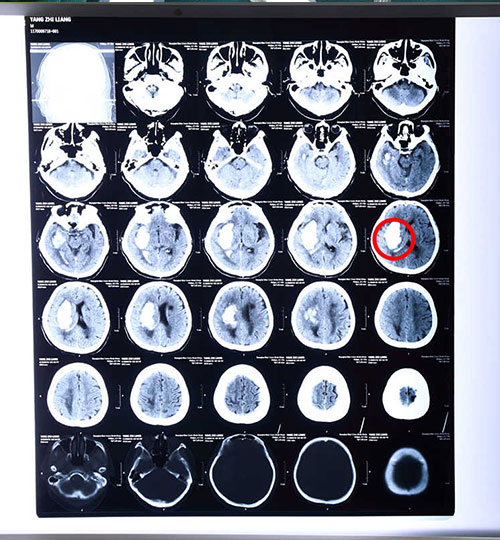

病人术前颅脑CT影像资料,红圈内白色阴影区为出血部位

据了解,脑出血是一种十分凶险的病症,一般大脑出血量达30毫升,若救治不及时便可能出现生命危险,而老人74毫升的出血量在临床上即使救治及时,其死亡率也可高达90%及以上,再加上老人年事高,且目前已呈嗜睡状态,状态较差,治疗也更有难度。